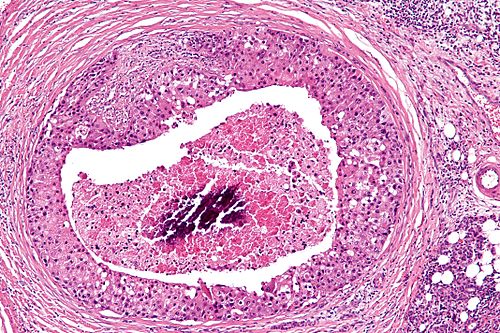

66 year old man, parotid mass.

Right parotid salivary gland.

Low magnification. H&E stain.